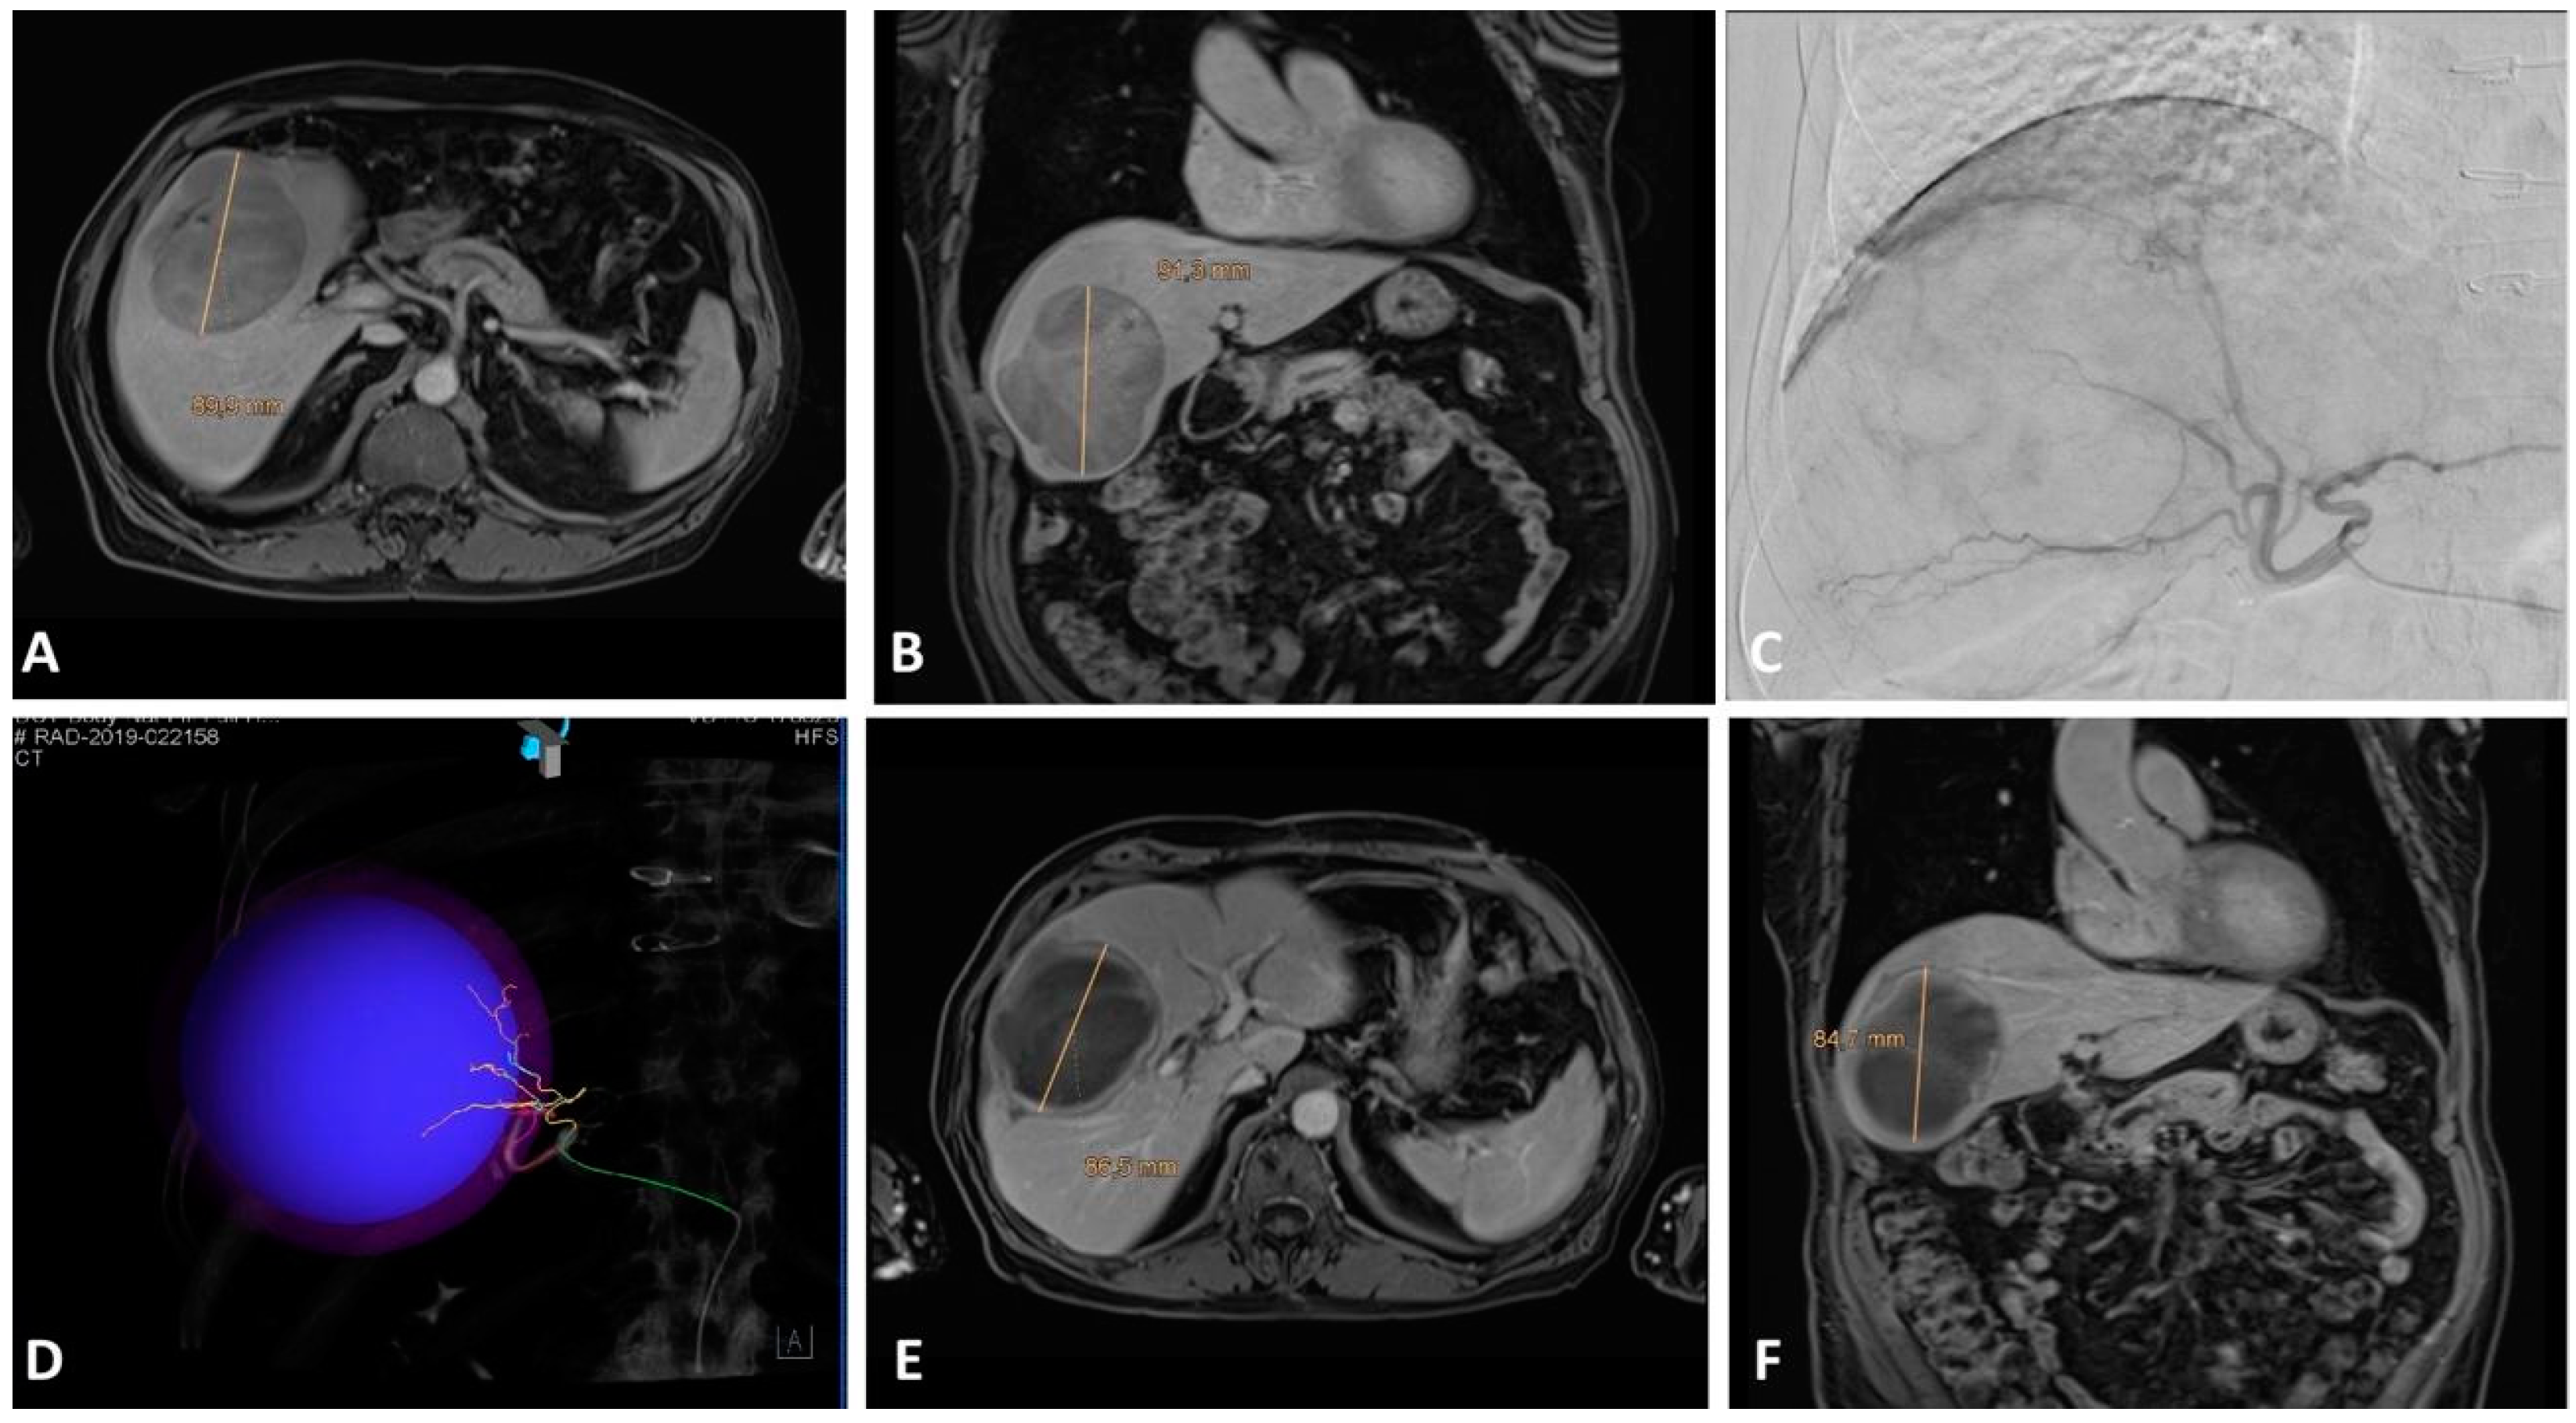

2. Local Ablation

2.2. Western Perspective